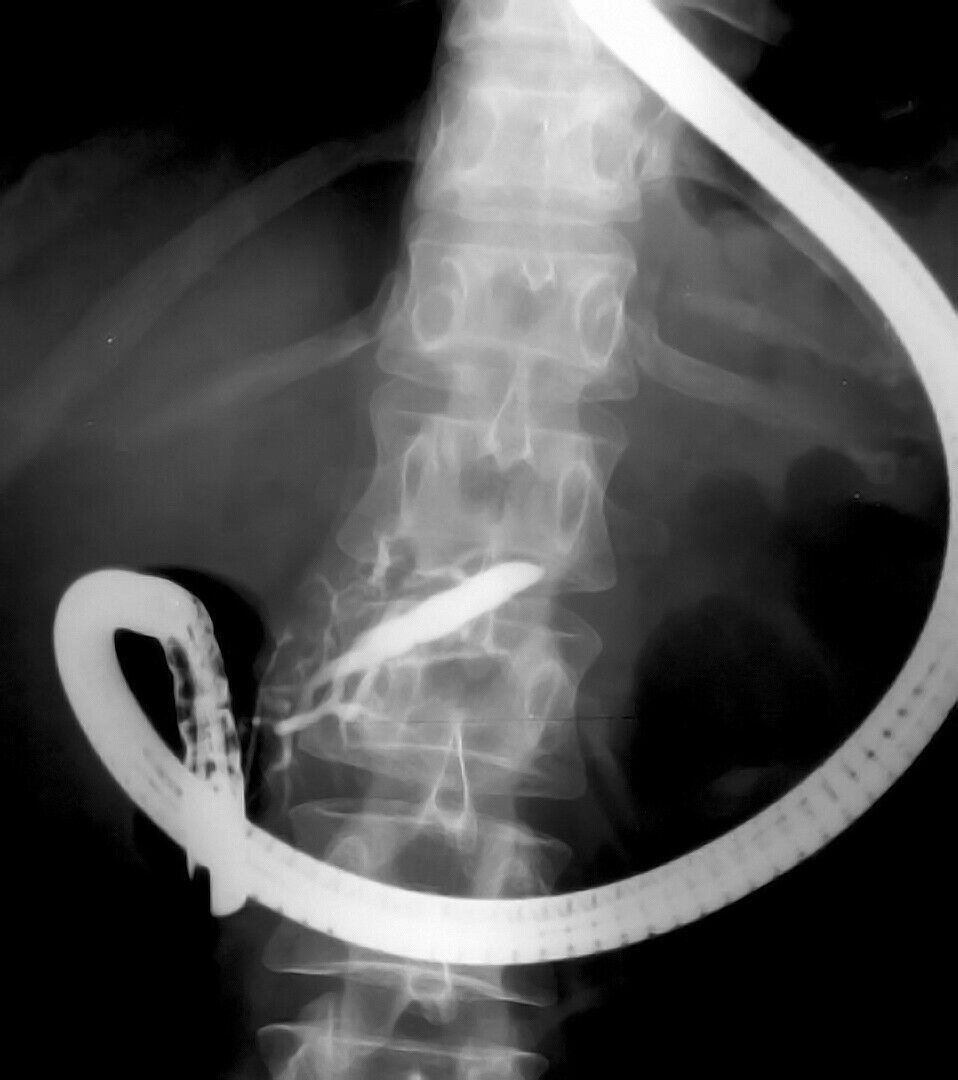

ERCP (Endoskopik Retrograd Kolanjiyo Pankreatografi), safra kanallarındaki taşların tedavisinde hangi avantajları sunuyor? Uzm. Dr. Adil Duman, bu yöntemin safra kanalları ve pankreatik kanalın incelenmesinde radyolojik tekniklerle birlikte özel bir endoskopi yöntemi olduğunu açıkladı. Safra kanalındaki taşların çıkarılmasında sıkça tercih edilen bu yöntem, hastaların şikâyetlerini hızlı bir şekilde gidermekte.

ERCP, cerrahi müdahalenin yerine neden tercih ediliyor? Uzm. Dr. Adil Duman, ERCP'nin başarı oranının yüksek olması ve komplikasyon riskinin az olması sebebiyle tercih edildiğini ifade etti. Ayrıca, safra kanalı ve pankreas kanserleri veya safra kesesi ameliyatları sonrası kaçak durumlarında da kullanılan bu yöntem, cerrahiye göre daha az risk içeriyor.

ERCP işlemi nasıl gerçekleşiyor ve ne gibi sonuçlar doğuruyor? Uzm. Dr. Adil Duman, ERCP'nin genellikle hastanın uyutularak yapıldığını ve işlemin ortalama 15-20 dakika sürdüğünü belirtti. İşlem sonrasında hastaların genellikle aynı gün taburcu edildiğini ve hızlı bir iyileşme süreci yaşadıklarını dile getirdi.